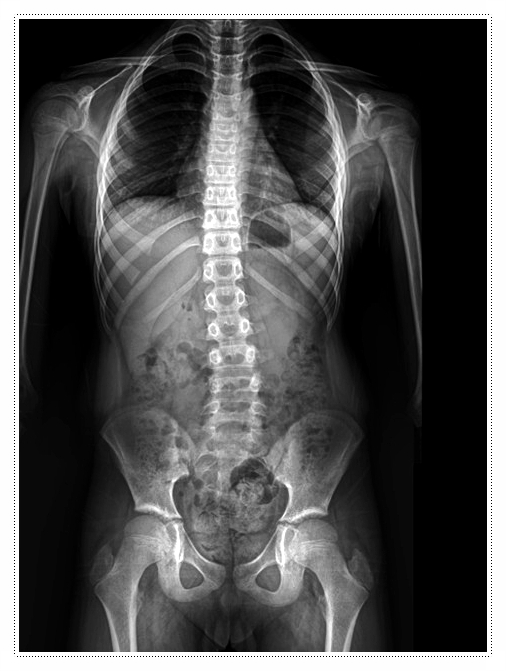

일반적으로는 X-ray 검사와 보행 분석 등을 통해 상태를 꼼꼼히 확인합니다.

뼈의 배열과 근육의 움직임을 파악한 뒤, 아이의 발 형태에 맞춘 맞춤 깔창으로 발 아치를 보완해 무릎의 부담을 줄이는 방식이 활용됩니다.

또한 한의사가 직접 손으로 골반과 척추를 교정하는 추나요법을 병행하기도 합니다.